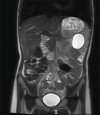

Epidermoid splenic cyst is a rare benign tumour in children, accounting for 10% of all cystic lesions of the spleen and is the most common diagnosis of non-parasitic splenic cysts. Its discovery could be incidental or happen after an imaging workup for a mass or abdominal pain. Since total splenectomy exposes a patient to the occurrence of overwhelming post-splenectomy infection, laparoscopic partial splenectomy has been increasingly popular over the past two decades because it preserves the immune function of the spleen. This technique should only be performed by a well-trained team because of the high risk of bleeding. The authors report the cases of three patients who underwent laparoscopic partial splenectomy: a 7-year-old girl with no relevant history with a 4.5-cm epidermoid cyst involving the lower pole of the spleen, a 13-year-old boy, type 1 diabetic on insulin therapy, with a 7-cm epidermoid cyst of the upper pole of the spleen and a 14-year-old girl, with no previous history, with a 6-cm upper pole epidermoid splenic cyst. Operating times were 2 h 30 min, 3 h and 4 h 30 min, respectively. The intraoperative blood loss was 100 mL, 350 mL and 300 mL, respectively. The length of hospital stay was 6 days for each patient. No blood transfusion was performed perioperatively. With a mean follow-up duration of 21 months (32 months, 21 months and 10 months, respectively), no complication or recurrence occurred.